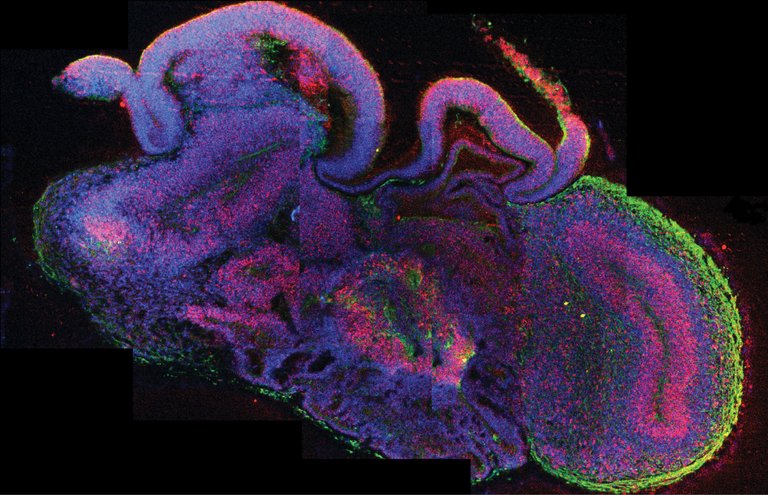

Giza zelula ametatik abiatuta garun txiki batera hurbiltzen den egitura bat sortzea lortu dute Austriako eta Erresuma Batuko ikertzaileek. Naturen argitaratu duten artikuluan garun-organoide deitu diote egitura horri, eta artifizialki sortutako garun bat izatetik oso urrun dagoen arren, benetako garunak dituen egituren antzekoak badituela azaldu dute. Nolabait, bederatzi hilabeteko fetu baten garunaren antzekoa da.

Hori egiteko, lehenengo zelula ama enbrionarioak hazi zituzten, ehun konektiboa imitatzen duen gel sintetiko batean. Gero, biorreaktore batean sartu zituzten, mugimenduan, ehunetara elikagai eta oxigeno nahikoa irits zedin. Hala, pixkanaka, zelulak ugaritu, eta ehunak osatu zituzten, ‘garuntxoak’ garatu arte. Odol-hodirik ez dute garatzen, eta, ikertzaileen esanean, hori izan daiteke gehiago ez haztearen arrazoietako bat. Izan ere, hiru milimetroko diametroa hartzen dute gehienera, bi edo hiru hilabetez hazi ondoren. Hala ere, biorreaktorean denbora luzez irauten dute: zaharrenek ia urte bete dute dagoeneko.